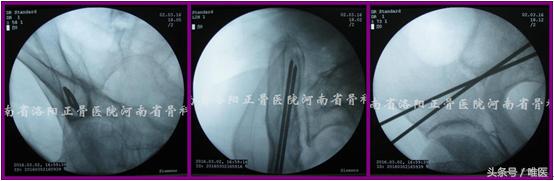

(1)确定进针点 透视出患侧骨盆Teepee像。两枚克氏针十字交叉放置于术区(AIIS尖部稍偏外侧)并调整,直至其交点正好位于Teepee像上“水滴”或“圆锥形帐篷”的中点(拟置入一枚螺钉时)或中点的稍尾端(拟置入两枚螺钉时)。应用亚甲蓝标记克氏针交点所对应的皮肤。于上述皮肤进针点做一长约1.0cm切口并钝性分离至AIIS。(图8)

图8. 确定进针点。

(2)置入导针 沿上述切口置入一枚无螺纹的空心钉导针至AIIS骨质。在骨盆Teepee像上确定针尖在“水滴”或“圆锥形帐篷”内的位置良好后将导针轻浅打入骨质,然后尽可能将导针调整成点状后再继续打入骨内(可保证导针沿安全通道的长轴行进而不会突破其周围骨质)(徒手操作时往往极难实现)。注意导针应避开安全区域的内下方以免置入过长时突入SIJ[17]。(图9)

图9. 置入导针。

(3)导针入位 如导针被成功地调整并维持成点状,则透视患侧的髂骨斜位像并在其监视下将导针打过骨折端至一定长度(避免超出髂骨后部即PSIS、PIIS骨皮质以免突入软组织内),此时导针必定位于髂窝薄弱骨质的尾端,GSN及髋臼头端。如未能将导针调整成圆点,尽管在髂骨斜位上其位置良好,仍需要追加透视患侧髂骨入口位像以确定其位于后部髂骨的内外板之间、IC之前进而避免其突入软组织及SIJ内。(图10)

图10. 导针入位。